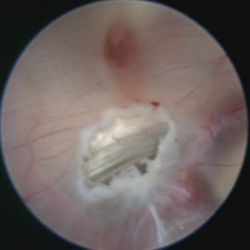

In diesen Fällen besteht die Behandlung mitunter in der Anlage eines alternativen Abflussweges aus dem Hirnwasserkammersystem in die das Gehirn umgebenden Zisternen (=Ventrikulozisternostomie). Dies geschieht durch einen minimalinvasiven, endoskopischen Eingriff. Ein Endoskop ist eine Art medizinisches Teleskop, das man über ein Bohrloch in die Hirnwasserkammern einführt. Da diese mit klarem Nervenwasser gefüllt sind, bietet sich eine gute Sicht auf die Wände und Strukturen der Kammern. Von oben kommt man durch eine Öffnung (Foramen Monroe) vom Seitenventrikel in den dritten Ventrikel. Mit feinen Instrumenten – wir verwenden routinemäßig einen Laser – wird der dünne Boden des dritten Ventrikels eröffnet

Das Nervenwasser kann nun wieder aus den Hirnwasserkammern ausfließen und so an die Stellen gelangen, wo es resorbiert wird.